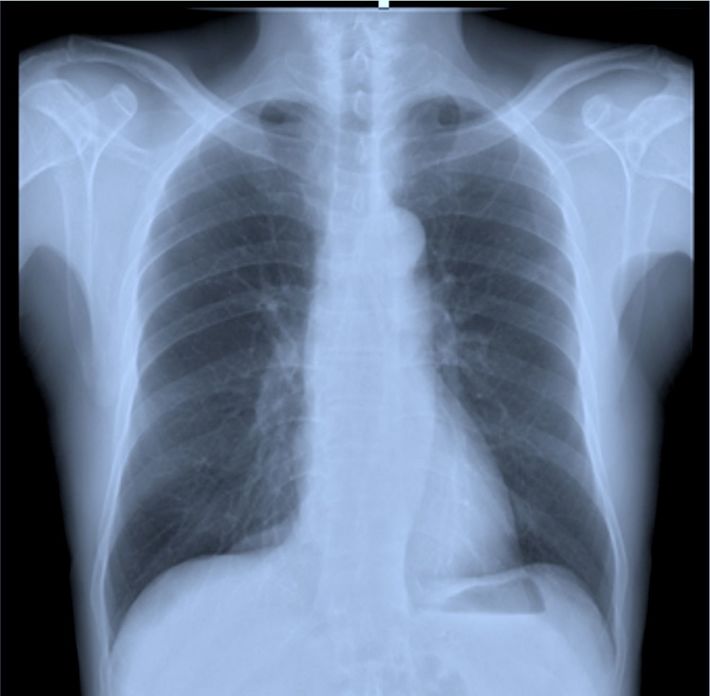

肺がん検診の「異常なし」を信じてはいけない…「もう手術はできない」と宣告され、7年闘病した40代男性の後悔

【画像3】胸部X線の画像では、肺と骨や臓器が重なって”死角”ができる

読影を行う、千葉大学名誉教授の長尾啓一氏